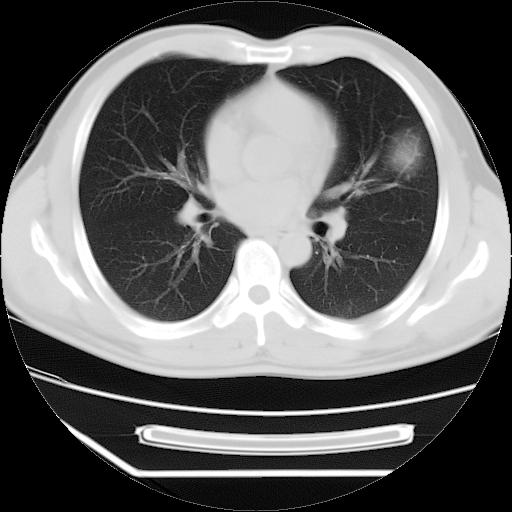

男,38岁,于2009年8月9日晚突发左侧胸痛,今x线提示左下肺阴影,为了明显确诊断,行ct检查,

血常规:嗜酸性细胞增高,单核细胞增高。

病灶发生在下叶,密度均匀,边缘模糊、毛糙,周围血管纹理增强扭曲改变,靠近胸膜处病灶胸膜反应明显。

支持考虑---球形肺炎。

左肺舌叶病变。主体病灶呈类圆形中心密度低,成液化趋势周边班片影分布

考虑肺脓肿

虽然实验室检查支持炎性病变,且病变内有坏死改变(中央呈大片状低密度影),但仍不能掉以轻心,鳞癌也可以有这种影像改变。